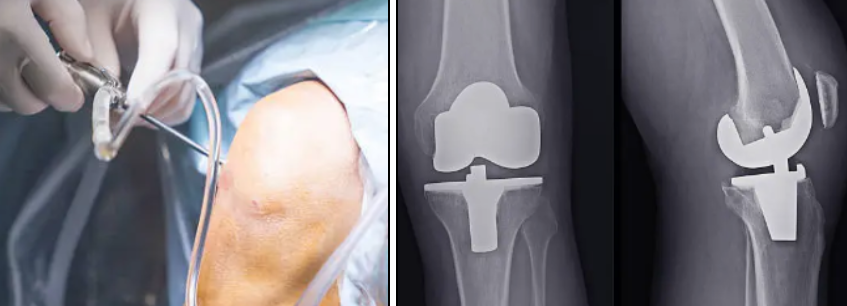

5. 수술적 치료(특정 상황)

관절경을 통한 관절 내 세척 또는 손상 조직 제거,

심한 경우 인공관절 치환술 등